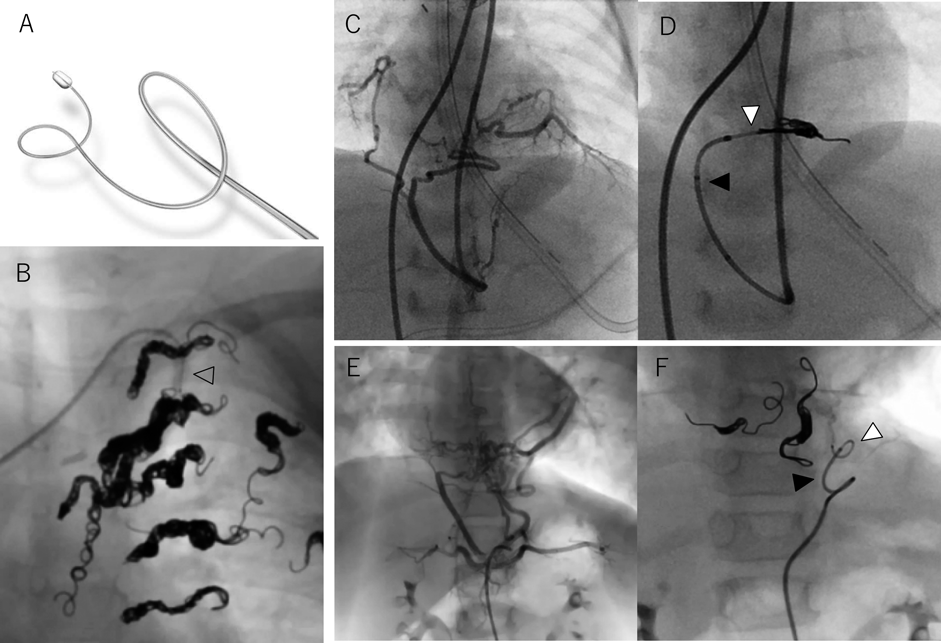

a.複雑に分枝した血管

Fig. 2 複雑に分枝した血管へのコイル塞栓

A, B)18歳フォンタン術後患者における外側胸動脈の塞栓.末梢分枝の径は1 mm以下であったが,Target™ XXLコイル6 mm×40 cm, 5 mm×20 cmでそれぞれの分枝(矢頭)に入り込んで(矢印)塞栓した.C, D)11歳フォンタン術後患者における複雑に分枝した体肺側副動脈(点線円)の塞栓.分枝の血管径は1~1.5 mmであったが,Target™ XXL 5 mm×20 cm×2本で分枝に入り込むように塞栓した(矢印).